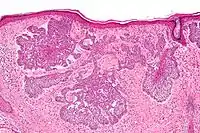

Nodular basal-cell carcinoma (also known as "classic basal-cell carcinoma") accounts for 50% of all BCC.[25] It most commonly occurs on the sun-exposed areas of the head and neck.[26]: 748 [27]: 646 Histopathology shows aggregates of basaloid cells with well-defined borders, showing a peripheral palisading of cells and one or more typical clefts.[25] Such clefts are caused by shrinkage of mucin during tissue fixation and staining.[28] Central necrosis with eosinophilic, granular features may be also present, as well as mucin. The heavy aggregates of mucin determine a cystic structure. Calcification may be also present, especially in long-standing lesions.[25] Mitotic activity is usually not so evident, but a high mitotic rate may be present in more aggressive lesions.[25] Adenoidal BCC can be classified as a variant of NBCC, characterized by basaloid cells with a reticulated configuration extending into the dermis.[25]

Palisading

Cleft.